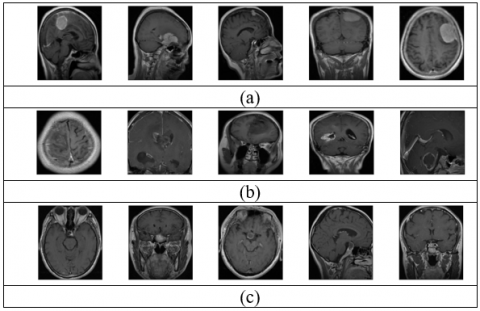

Figure 3. Cropped images for tumor (a) meningioma (b) glioma (c) pituitary

We have generated two datasets from the original image dataset. One dataset with cropping operation around the brain view in the MRI image and another one without cropping operation. The variation between two datasets shown in the Figures 2 and 3. Two datasets are normalized and resized to 256x256 pixels. The original size of the image is 512x512 pixels. We have used two size of images for input layer of the network. We did not identify any noted improvement in the accuracy rate of classification and consumed more resources in terms of memory and processing time for the dataset of 512x512 pixels compared to the dataset of 256x256 pixels.